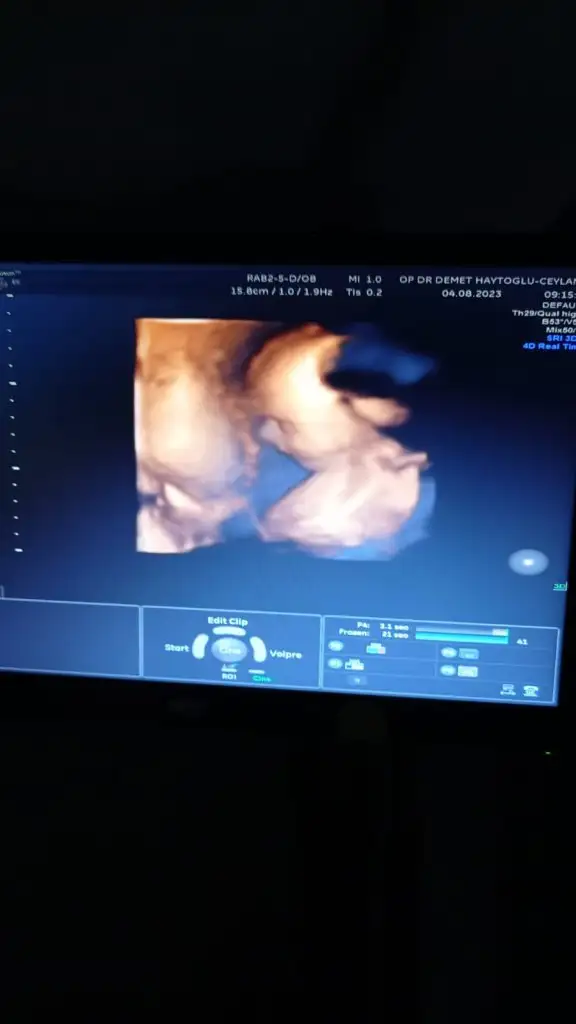

Evet canım gerçekten öyle.Bebeğimde iyiydi çok şükür o yüzden daha iyiyim.Yarın homoffice çalışacağım umarım geçerAh geçmiş olsun neyseki doktorun her şeye bakmış aklında soru işareti kalmasın artık. Ama gerçekten dinlenmek gerek, ben bazen unutup hızlı hareket ediyorum falan hemen belli ediyor kendini.